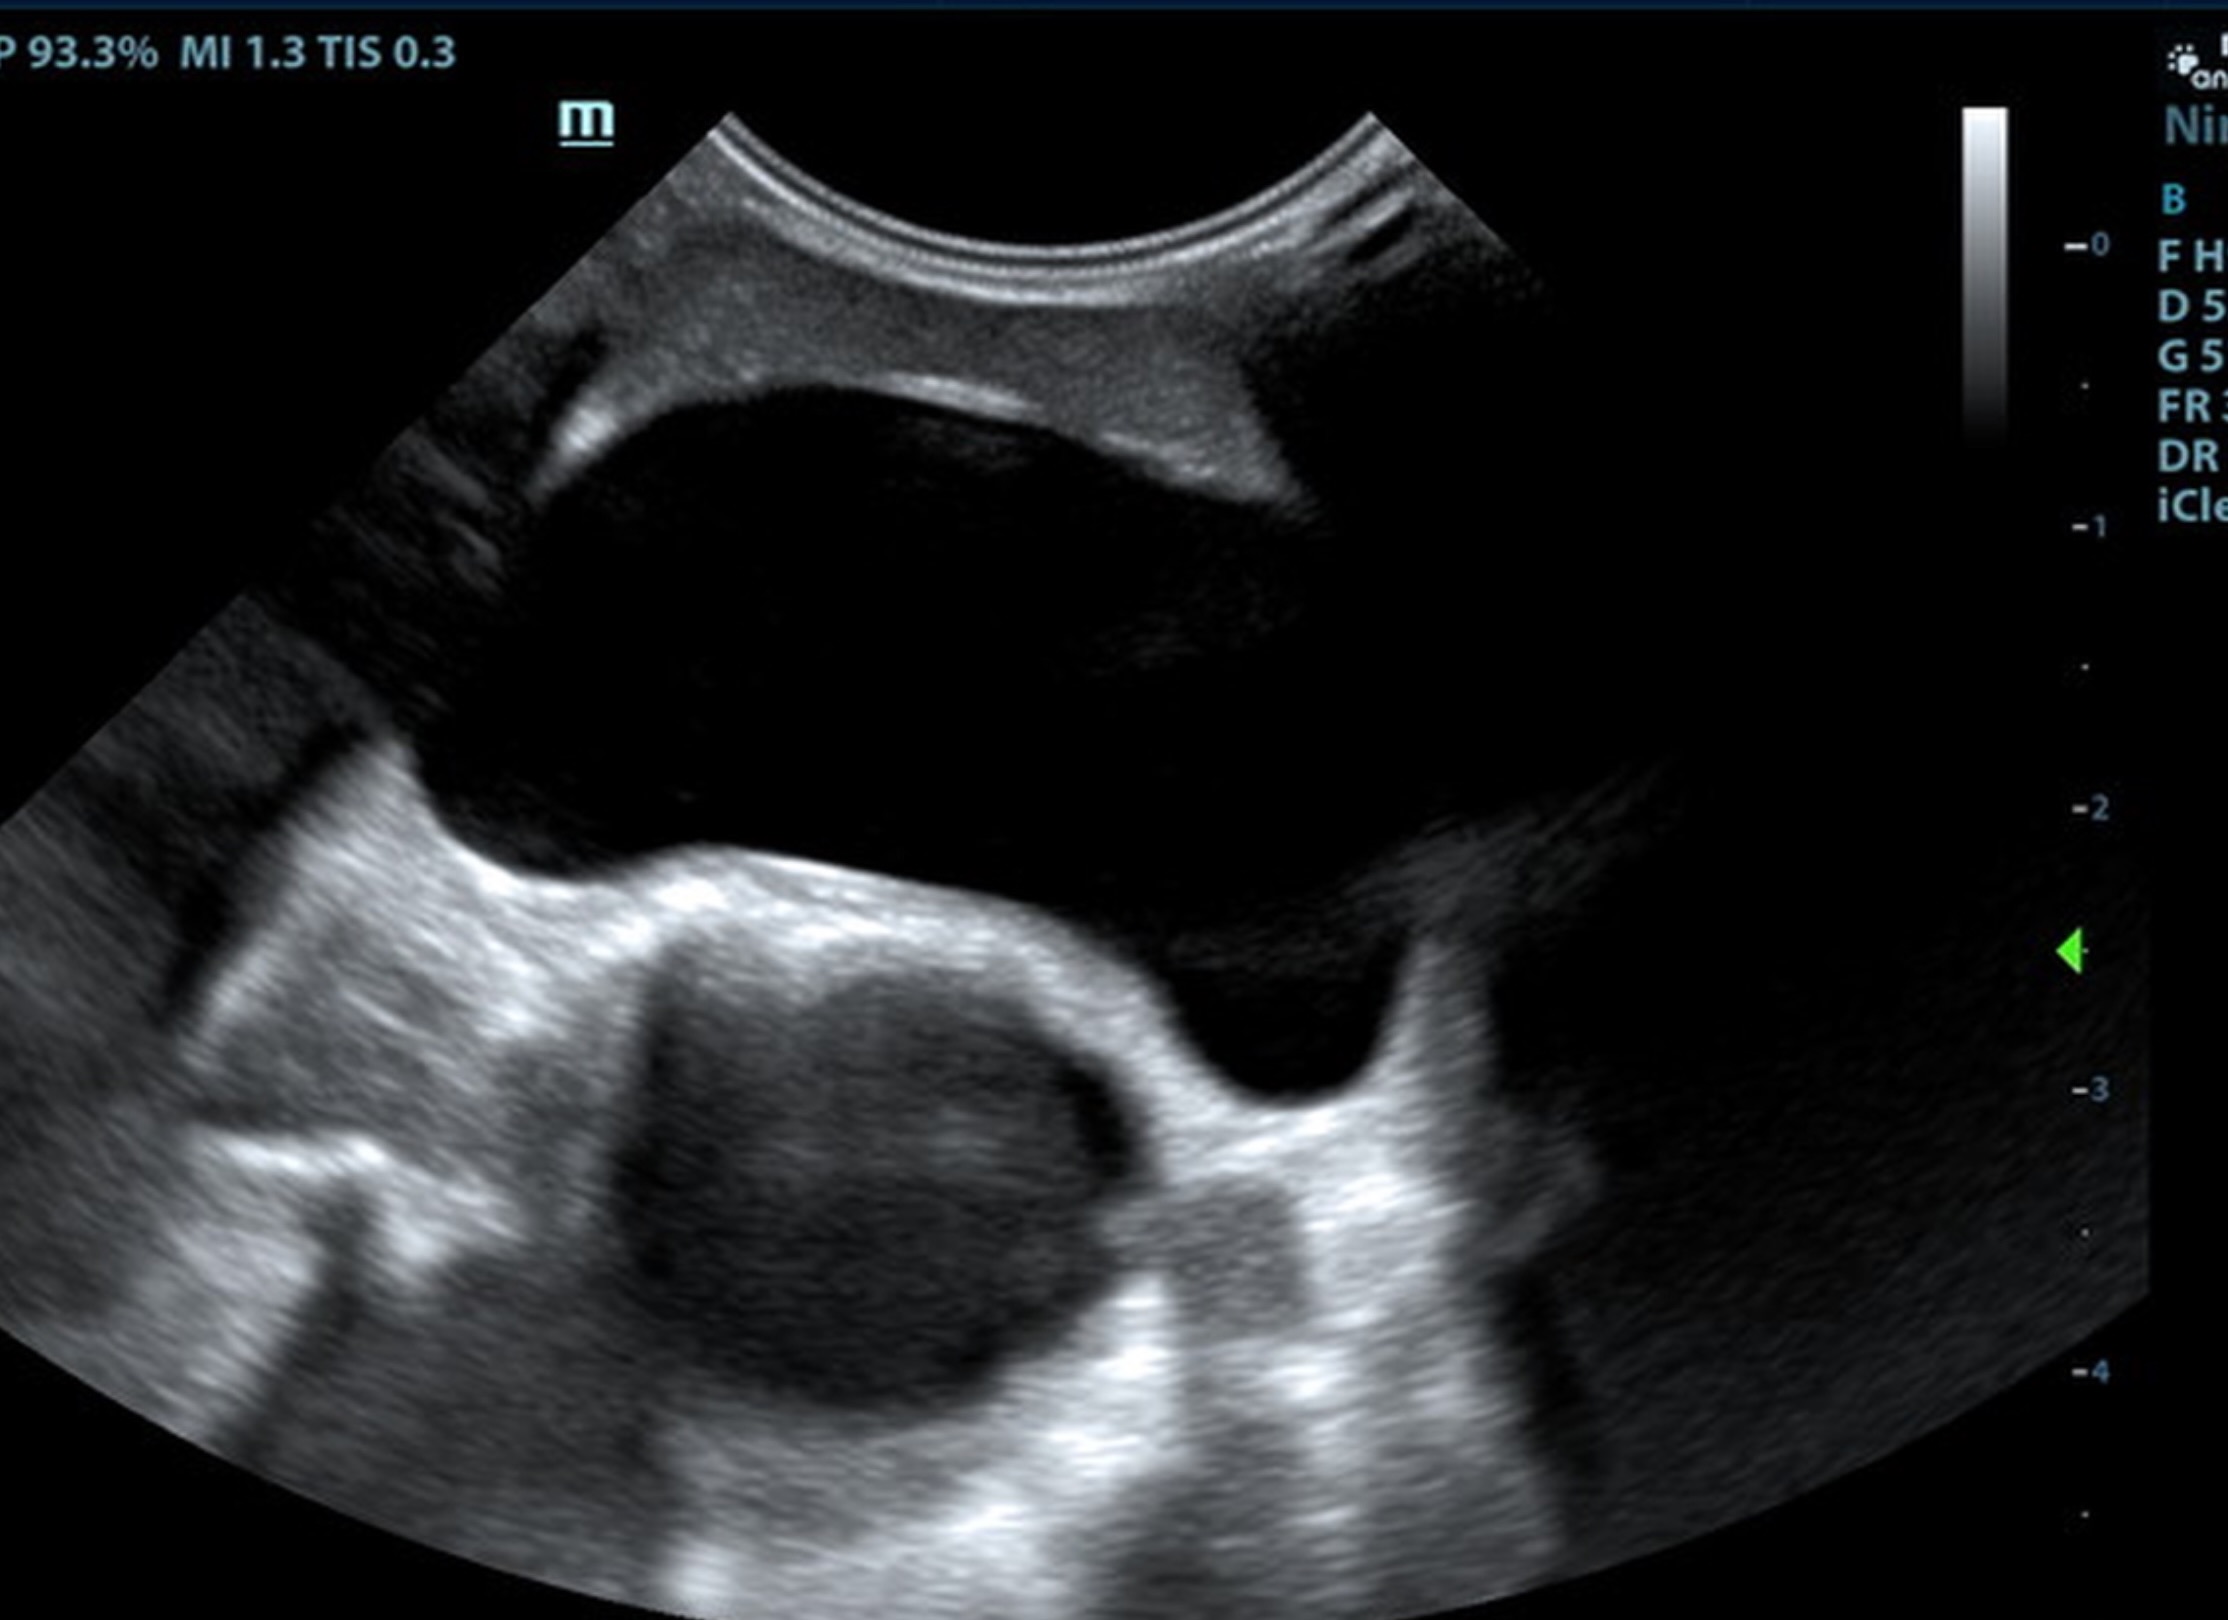

The liver was subnormal in size, yet the portal vein and vena cava ratio was 1:1. The portal veins were subnormal in size and measured 0.34 cm. The vena cava was enlarged and measured 0.34 cm. The vena cava was enlarged and measured 0.72 cm, aorta measured 0.4 cm. The branching of the portal vein appeared to be normal and of adequate volume. The portal vein and vena cava measured 0.5 cm each in the extrahepatic space. The splenic vein entry into the portal vein and gastroduodenal vein entry into the portal vein appear to be normal. There was one turbulent vessel in the region of the central branch of the portal vein, which may represent an intrahepatic shunt, but this could not be confirmed. The width of the shunt is approximately 0.76 cm. This is in position of central divisional shunt; however, right divisional origin cannot be completely ruled out. The gallbladder presented acceptably thin walls with primarily anechoic content. The cystic and common bile ducts were normal.